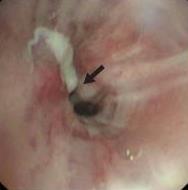

• 侵袭性肺真菌病的支气管镜表现及介入治疗效果

2025, 31(9):81-90. DOI: 10.12235/E20250317

摘要 (112) HTML (56) PDF 6.06 M (77) 评论 (0) 收藏

摘要:目的 探讨侵袭性肺真菌病(IPFD)的支气管镜表现,并评估介入治疗的安全性和疗效。方法 回顾性分析2018年5月12日-2025年5月12日于该院行支气管镜检查的35例IPFD患者的临床资料,观察IPFD的支气管镜表现及介入治疗效果。结果 共收集35例患者临床资料。其中,男22例,女13例,患者年龄(53±14)岁。基础疾病包括:血液系统恶性肿瘤10例,长期应用糖皮质激素者5例,2型糖尿病者4例,肺部恶性肿瘤2例,器官移植1例。胸部CT显示:肺部病变累及单肺叶者19例,累及多肺叶者16例。支气管镜下表现主要为:黏膜充血水肿29例(82.9%)、坏死物堵塞管腔22例(62.9%)、大量黏稠脓性分泌物17例(48.6%)、支气管部分狭窄或闭塞16例(45.7%)、黏膜坏死9例(25.7%)、黏膜出血5例(14.3%)、真菌球3例(8.6%)。其中,32例(91.4%)接受全身性抗真菌治疗,17例(48.6%)接受支气管镜局部两性霉素B灌注治疗,10例(28.6%)采用活检钳钳除病灶,6例(17.1%)采用冷冻探头冻取病灶,4例(11.4%)接受氩气刀治疗。28例(80.0%)临床症状明显改善,肺部影像学病灶缩小或消退;4例(11.4%)病灶稳定;3例(8.6%)未完成治疗。结论 IPFD多见于免疫抑制宿主,支气管镜常表现为:坏死物堵塞管腔、伴脓性分泌物、支气管管腔狭窄和局部黏膜充血水肿或坏死。全身抗真菌药物联合支气管镜下介入治疗,安全性高,且疗效好。